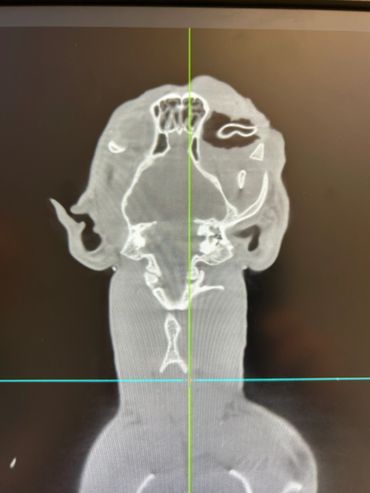

At Harborside Animal Hospital in Clearwater, FL, we are proud to offer CT imaging for pets with fluoroscopy capability. This advanced imaging modality allows us to provide affordable veterinary imaging solutions to the surrounding areas. Our services include evaluations for conditions such as elbow dysplasia, abdominal masses, aural polyps, chronic ear infections, sub lumbar lymph node metastasis checks, contrast-assisted mass spread mapping, complicated oral disease, nasal masses, thoracic metastasis checks, portosystemic shunts, angular limb deformities, collapsing trachea, and urinary contrast studies. Thank you for entrusting us with your patients.